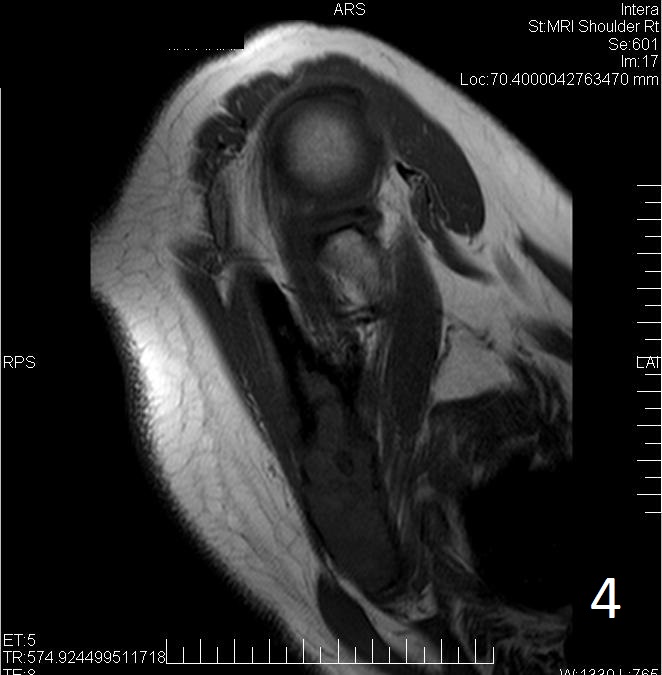

• MRI can have a very variable appearance and enhancement pattern; May not follow same signal as fibrous tissue which is normally Low signal on T1 and T2

• Low-intermediate heterogenous signal on T1 (Fig. 4)

Fig. 4. Axial T1W of fibrous dysplasia of the scapula shows a lesion with similar signal intensity as muscle.